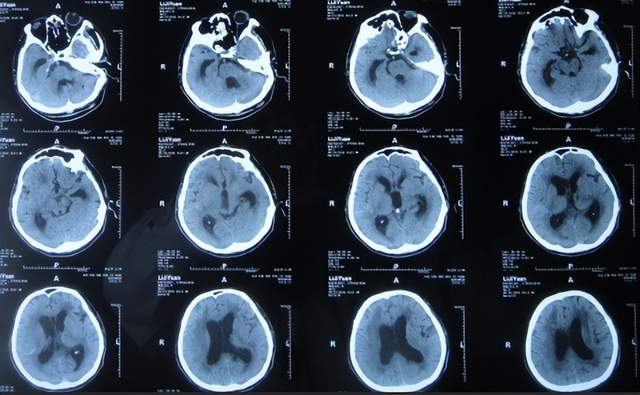

腰大池引流术后4天即2021年9月12日,查头颅CT示脑室内积血基本消失(图-5)。

图-5:2021年9月12日头颅CT

腰大池引流术后8天即2021年9月20日,给予拔除腰大池引流管,之后给予保守治疗。

拔除腰大池引流管后3天即2021年9月23日,查头颅CT示(图-6)后继续给予保守治疗。

图-6:2021年9月23日头颅CT

腰大池引流管拔除后13天即2021年10月3日,患者恢复至可以搀扶下行走约20米,能简单言语,查头颅CT较2021年9月23日认为没有明显变化(图-7)。

图-7:2021年10月3日头颅CT

但继续保留治疗20余天的时间内,患者逐渐出现意识变差,走路变差,至2021年11月3日(腰大池引流管拔除后31天),病情变重致不能走路,不能言语,查头颅CT(图-8)后考虑脑积水,给予腰椎穿刺治疗。

图-8:2021年11月3日头颅CT

但腰椎穿刺治疗7天病情无明显改善,于2021年11月10日(住院治疗2月余)出院回家休养,出院时头颅CT示仍有脑积水(图-9);出院时:意识差,不能走路,不能言语。

图-9:2021年11月10日头颅CT